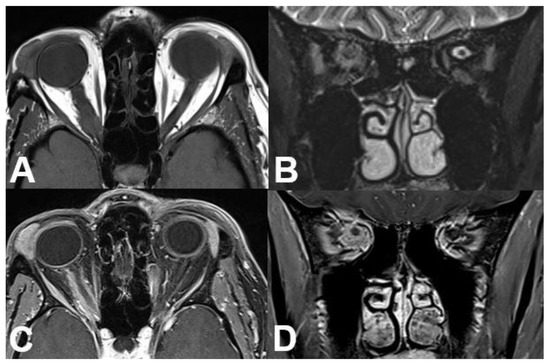

3.2. Intraconal Tumors

3.2.1. Venous Varices

3.2.2. Cavernous Hemangioma